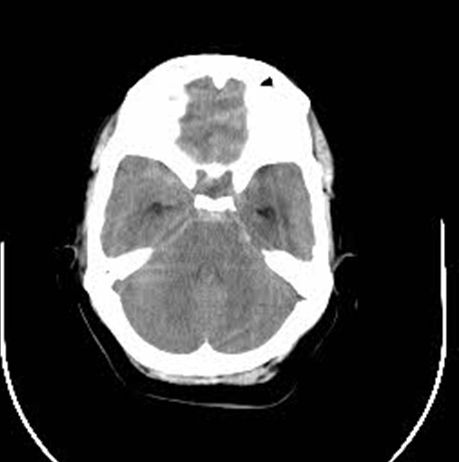

Background: Cavernous hemangiomas are common benign vascular malformations. Their existence in the intraventricular region is very rare. Case Reports: A 43-year old woman with an occipital headache was admitted to the emergency ward. Brain computed tomography scan showed mild hydrocephalus and multiple intraventricular isodense lesions. Imaging findings, especially of Gradient Resonance Echo imaging, were in favor of multiple intraventricular cavernous malformations. Conclusion: This is a rare presentation of multiple cavernous malformation as occipital headache without needing surgical intervention in this phase. Coexistence of periventricular plaques like Radiologically isolated syndrome of Multiple sclerosis is another unique aspect in this report. [GMJ.2017;6(1):61-65]